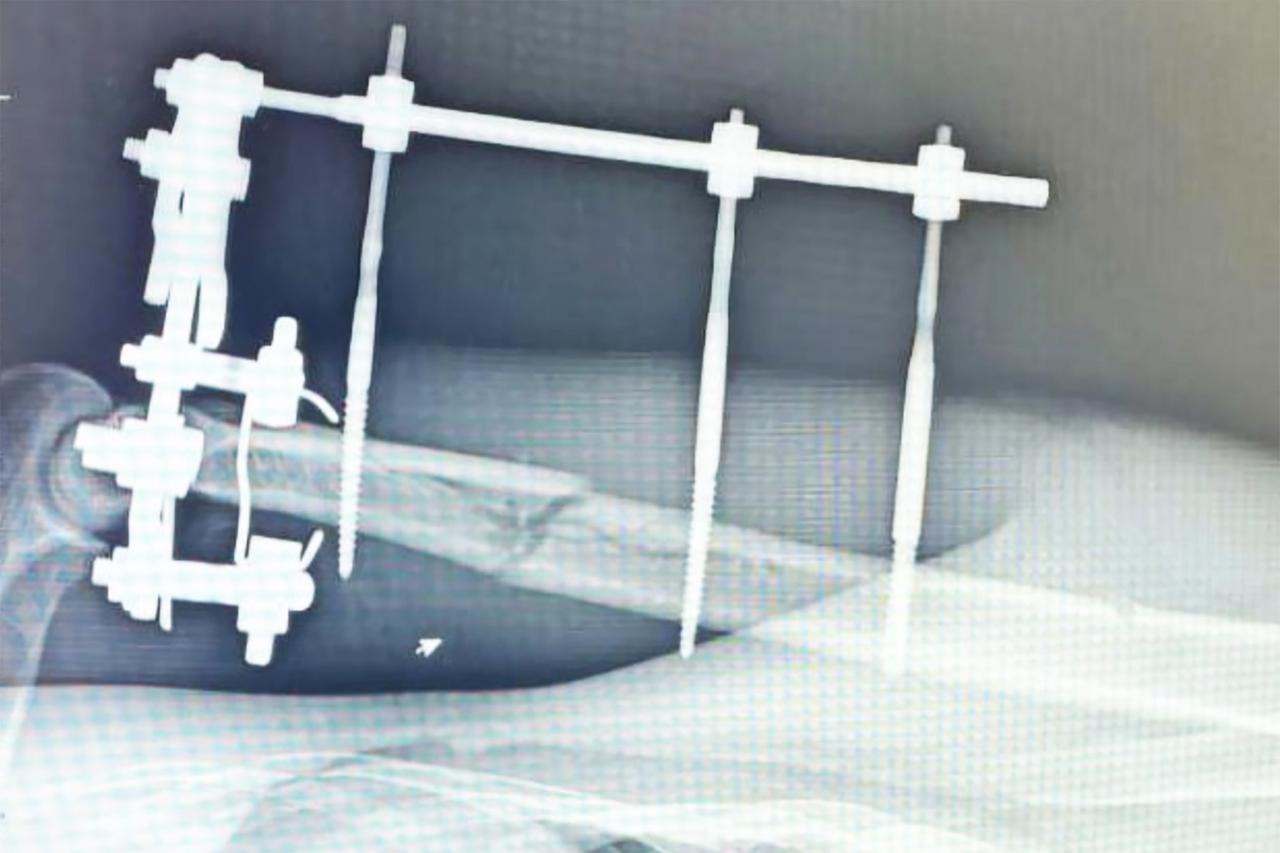

Врачи провели хирургическую обработку поврежденной конечности и зафиксировали ее в необходимом положении. После при помощи аппарата Илизарова специалисты выполнили остеосинтез. Всего пациенту потребовалось почти полтора месяца на восстановление. Даже после выписки ему порекомендовали продолжать наблюдаться у травматолога.